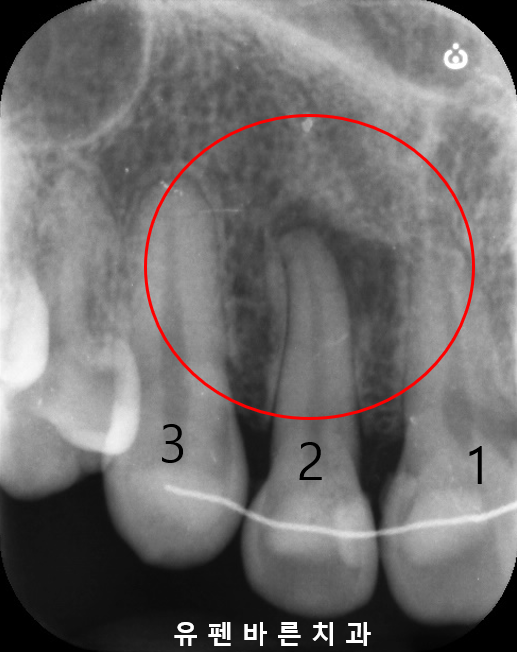

오른쪽 사진의 2번치아 보이시나요?

더 자세히 살펴보기 위해 작은 엑스레이를 찍어보았더니

눈에띄게 뿌리끝이 검은색 염증으로 둘러쌓여 있네요.

유펜바른치과에서는

염증을 없애기 위해 신경치료를 먼저 진행하고,

뻐드러진 앞니 치아와 맞닿는 부위를 인비절라인을 통해 개선할 수 있도록 진행해 드렸어요.

신경료를 마치고 나니

확연히 염증의 크기가 줄어들었습니다^^